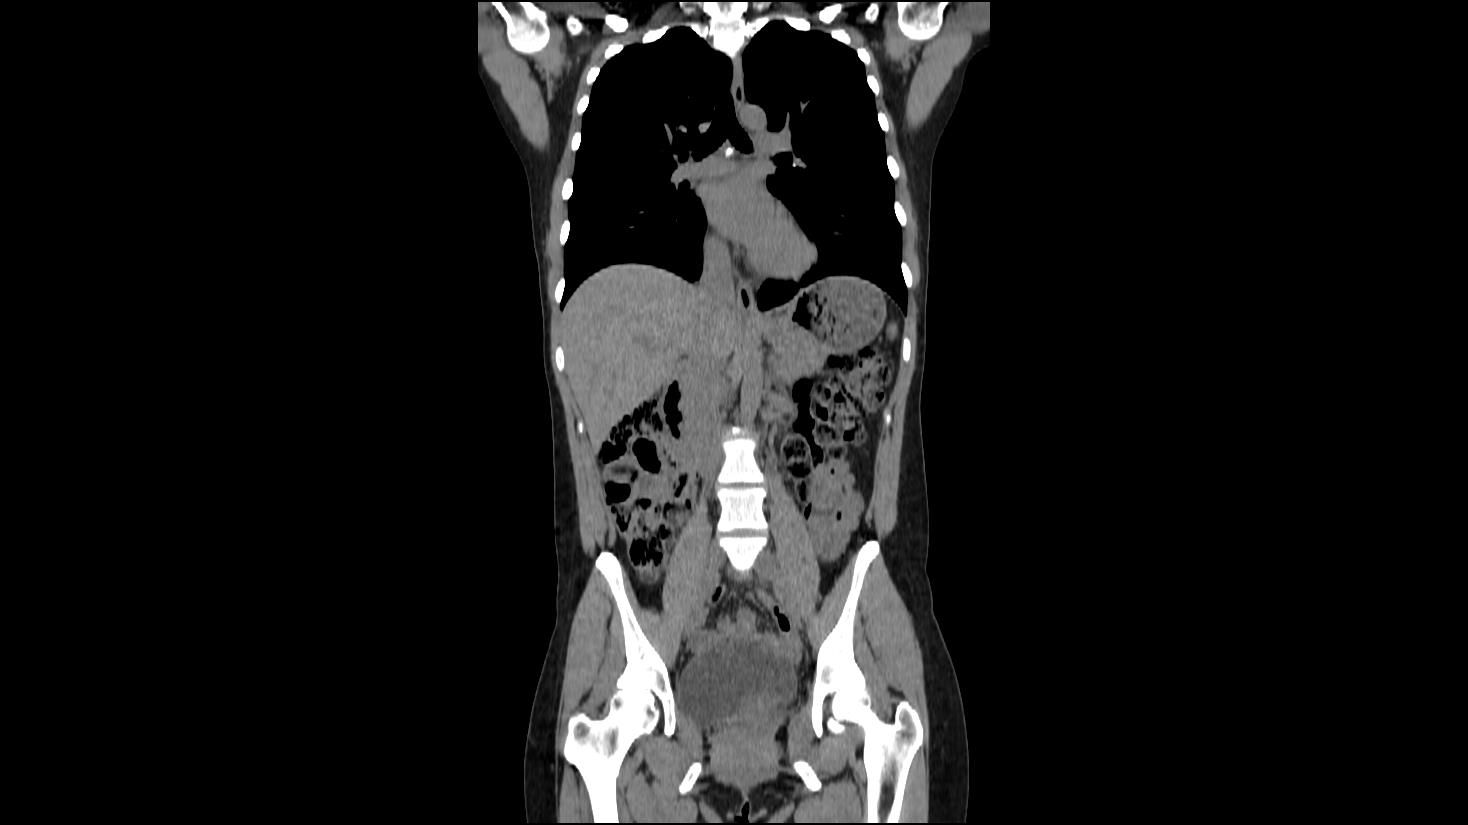

A Full Body Scan That Detects Risks Before They Grow

A full body scan gives you a fast view of your chest, abdomen, and pelvis. This early look helps detect tumors, cysts, stones, and other silent problems that may grow without warning. Many of these concerns do not cause pain or symptoms for months or even years. That is why so many people choose full-body imaging as a preventive step in their long-term wellness plan.

With detailed CT images, your scan can reveal issues that most routine exams cannot find. This allows you to understand your health clearly and gives you more time to talk with your provider about the next steps. It also provides peace of mind when your scans show that everything looks stable.